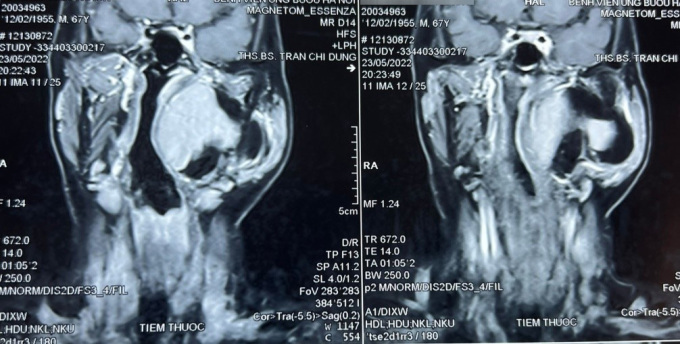

Bệnh nhân đến khám vì khối sưng phồng vùng mang tai trái, không kèm theo khó chịu hay đau đớn. Qua thăm khám, bác sĩ phát hiện một khối u lớn vùng cổ kích thước khoảng 10 x 8cm, thuộc khoảng bên họng, trải dài từ nền sọ xuống hạ họng, đẩy lệch thành bên họng vào trong. Khối u gồm 2 phần, phần nông nằm dưới tuyến mang tai và phần còn lại nằm sâu hơn.

Theo kết quả kiểm tra, đây là khối u lành tính nhưng phức tạp. Thông qua hội chẩn, các bác sĩ quyết định tiến hành phẫu thuật sớm lấy bỏ khối u tránh nguy cơ khối u chèn ép vào đường thở, đường ăn, thần kinh, mạch máu và các thành phần liên quan khác.